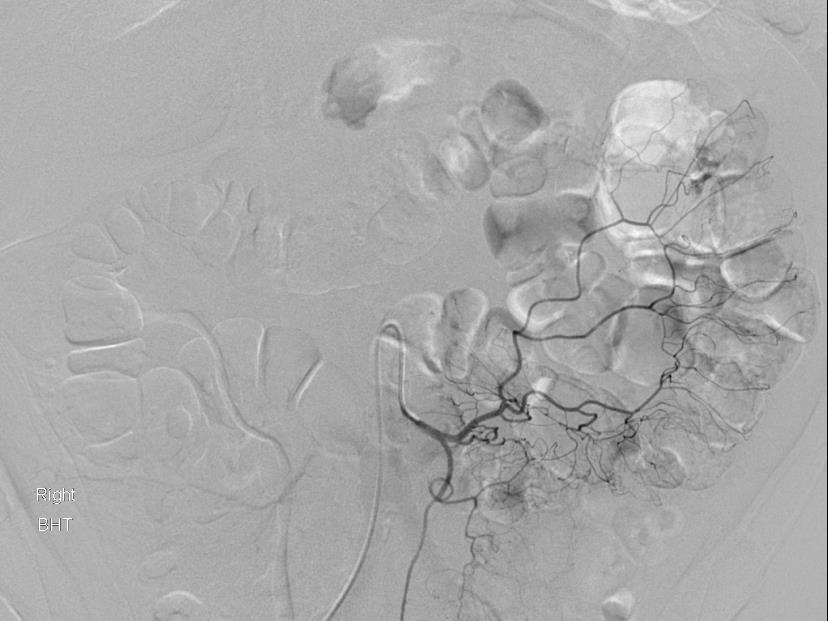

Lenhart 等人报告Onyx胶用于消化道出血的栓塞,2个中心共16例病人,其中6例为典型的消化道出血,其它为假性动脉瘤,创伤和肿瘤[7]。 ![]() 64M 结肠憩室直肠鲜血便历史,此次出血输入5单位血后,收缩压 80mmHg